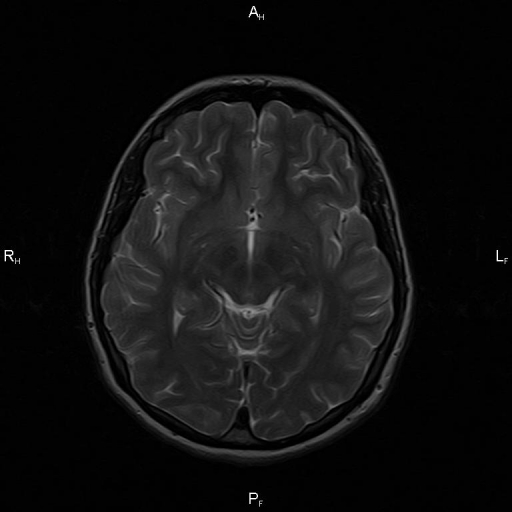

МРТ снимки мальформации Денди-Уокера